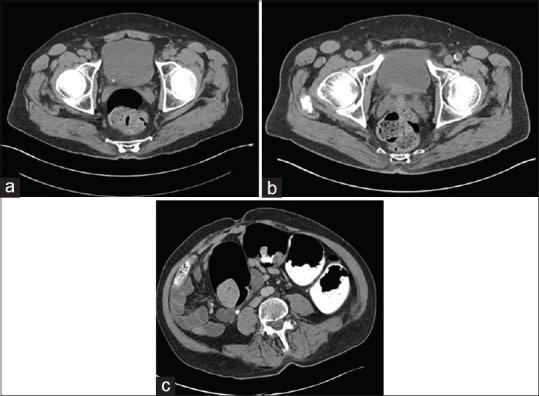

Retrograde ureteric calculus migration is a rare phenomenon. Herein, we report two such cases where each patient presented with a calculus, measured at 5 mm and 6 mm, respectively, at the vesicoureteric junction (VUJ) on noncontrast computerized tomography kidneys, ureters, and bladder (CTKUB). Following acute presentation with renal colic, each patient opted for conservative management of their ureteric stone and became asymptomatic when undergoing their follow-up imaging. The first patient underwent a follow-up noncontrast limited pelvic computerized tomography (CT) where it had appeared that the radiolucent VUJ calculus had passed. This stone was then discovered incidentally 3 months later in the upper ureter when the patient had undergone a CT colonography. The other patient underwent a follow-up X-ray KUB where the stone was shown to have migrated to the lower renal pole calyx which was confirmed with noncontrast CTKUB imaging. In all reported cases of retrograde VUJ calculus migration, the use of a noncontrast limited pelvic CT scan either missed or would have missed this phenomenon. This potential pitfall of the noncontrast limited pelvic CT scan should be appreciated and the use of full upper renal tract imaging should be considered for the follow-up of radiolucent VUJ calculus cases whereby there is no clear history of calculus passage.